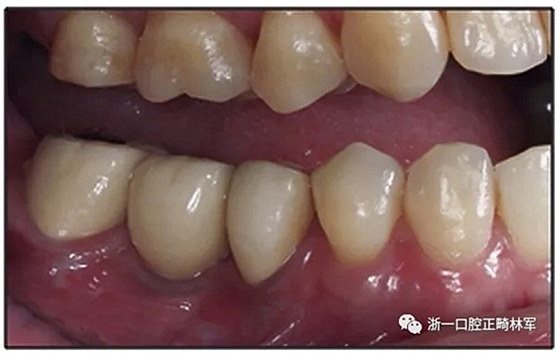

圖15.A,去除固定裝置一個月后,下頜左側第二前磨牙復發(fā),移動到種植體愈合的部位; B,B-0表示開始再治療,通過鏈圈和推簧的矯正復發(fā); C,B-9是治療結束后3個月回訪時下頜弓的咬合面觀,這是再治療階段的9個月。下頜左側第二前磨牙和第三磨牙的頰面粘合一個固定保持器,以防止復發(fā)。